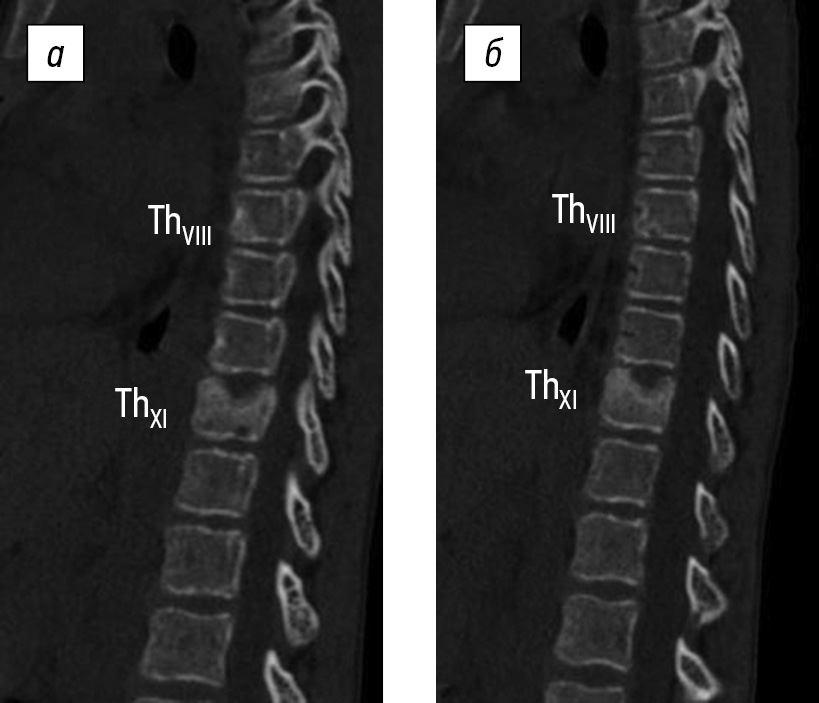

The final diagnosis was NBO, multifocal form. Therapy continued with nonsteroidal anti-inflammatory drugs. Ibandronic acid therapy was initiated at a starting dose of 1.5 mg, with subsequent infusions every 3–4 months at a dose of 2 mg, according to the decision of the off-label medical committee. The therapy scheme was borrowed from A. Dhanrajani and R.P. Khubchandani (2018) [12]. Ibandronic acid was administered to the child in 250 mL of 0.9% sodium chloride solution over 3 h using an infusion machine at a rate of 2 mL/min. The child received five consecutive infusions of ibandronic acid. The efficacy of the therapy was confirmed by imaging methods supplemented by clinical data. After the first administration of the medication, the mother observed an enhancement in the child’s overall health, an increase in motor activity, and a reduction in pain. The child tolerated the treatment regimen well, and no adverse reactions were detected either early or late. The laboratory results indicated a decrease in the ESR levels to normal. Radiation dynamics were evaluated sequentially after the second and fourth infusions. Following the fourth infusion of ibandronic acid, CT data revealed the complete restoration of the integrity of the bone structure of the anterior and posterior walls of the frontal sinuses. Inflammatory changes on the side of vertebral bodies were reduced after the second infusion, and the final subsidence of spondylitis was observed after the fourth infusion (Fig. 5). No new foci of destruction were observed during treatment.

Fig. 5. Magnetic resonance imaging of the thoracolumbar spine after four consecutive infusions of ibandronic acid. No signs of trabecular edema of the vertebral bodies are observed. In the central-left section of the ThXI vertebral body, deformation of the upper lamina is determined as a local indentation with a zone of fatty transformation of the bone marrow and areas of limited sclerosis. The height of the ThX–ThXI disk is moderately reduced without significant reduction in its signal